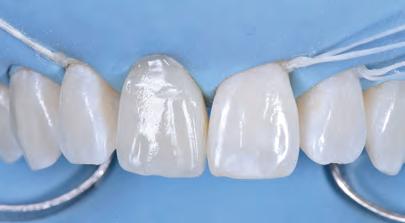

5: A treatment mock-up may be fabricated in a flexible machinable polycarbonate based on the contours of a final proposed restoration, in such a manner as to be capable of fitting to the contours of the pre-operative situation.

At the laboratory, the dental technician may merge these digitised records using Zirkonzahn.Modifier software (Zirkonzahn Srl; Gais, Italy) to form a precise 3D rendering of the patient’s pre-operative dentofacial situation, with all biomechanical and aesthetic landmarks conveniently available for reference. This offers the technician unparalleled, high-fidelity access to key diagnostic clinical information when compared to conventional analogue-based workflows.4 At this stage, an end goal of prosthodontic treatment may be developed wherein the contours of the proposed restorations are informed on the basis of the patient’s physiognomy, or rather, their unique and characteristic facial features (Figure 4).9 The final proposed design may be fabricated into a snap-on smile try-in, or treatment mock-up, using a flexible machinable polycarbonate (Temp Premium Flexible; Zirkonzahn Srl, Gais, Italy) (Figure 5).

Visualise before you provisionalise

At this early stage of diagnostic work-up, prior to any operative intervention, the clinician and the technician can now communicate to each other and, most importantly, to the patient, in an understandable visual rhetoric, a precise end goal of treatment from which a meeting of the minds may be achieved (Figures 6 and 7).5